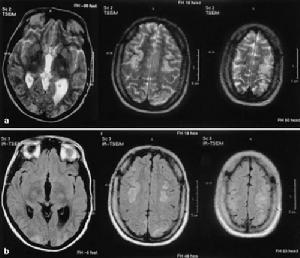

兩側半卵圓中心側腦室旁深部腦白質呈不甚對稱的長T1WI長T2WI信號,無占位效應,在T1WI圖像上呈低信號,T2圖像上呈高信號,全部病人腦室擴大,腦溝增寬,腦池擴大,表現為腦萎縮特徵。78例(89.6%)為多發性腦梗塞,9例(10.3%)為單發性腦梗塞,其中6例(6.9%)伴出血灶,男2例,女4例,其13例(14.9%),CT未發現腦梗塞,由MRI明確診斷。主要是對腦內脫髓鞘改變的範圍和腦萎縮的程度,特別是塞灶的大小,部位,腦缺氧早期診斷是否合併出血,這樣,對患者確定治療方案及預後有著深遠的意義。

影像學表現:CT表現為斑片狀及斑點狀低密度影,MRI表現為點狀及片狀長T1WI長T2WI信號,由腦深部灰質團塊萎縮,胼胝體繼發變薄,致使腦室擴大,又由於瀰漫性髓鞘脫失而有不同程度的腦萎縮,顯示腦溝增寬,腦池擴大(如圖1~4)。有高血壓及動脈硬化的病理基礎也可發生腦出血是腔隙性梗塞的直接原因。

賓斯旺格病診斷及鑑別診斷:CT,MRI的問世,為本病的生前診斷提供了影像學依據,CT表現為雙側腦室旁白質區與半卵圓中心顯示散在性或融合性低密度區,對稱或大致對稱,基底節,內囊與丘腦區可見多發性腔隙性梗塞,重者伴腦室擴大,其室管膜面多參差不齊,呈碎布狀。MRI表現:在腦室周圍白質與半卵圓中心顯示散在或融合性病變區,T1WI呈黑色,T2WI呈白色。重度與中度顯示腦室擴大,腔隙性梗塞顯影清晰,病灶數目比CT發現的多。SAE應與多發硬化,嚴重腦積水所致的室管膜水腫,CO中毒腦水腫期,腦囊蟲病腦炎型,ALZHEIMER氏病,PICK病,及其他特異性腦白質病,這些腦白質病變根據CT,MRI的表現特點,結合臨床表現60歲以上潛隱起病,逐漸加重,若具備卒中發作,高血壓,慢性進行性痴呆三大臨床特徵,綜合分析,即可做出診斷,也可隨訪複查。

SAE經CT,MRI檢查可明確診斷,CT檢查在發病24h內往往陰性,顯病灶數目少,腦幹,後顱窩病變及視神經通路(視放射)的損害未能顯示而遺漏,但CT價格低,易普及,對腦組織缺氧24h後,CT值即降低,並對缺氧引起的顱內出血及出血量有客觀指標。而MRI在診斷SAE方面比CT更優越,表現在:①MRI在腦細胞毒性水腫6h即可發現病變。②MRI發現病灶數目多。③MRI能夠清楚顯示腦幹,後顱窩病變及視神經通路,顳角部位病變。④MRI可行矢狀,冠狀掃描,多方位觀察。⑤MRI可顯示VIRCHOWROBIN間隙。